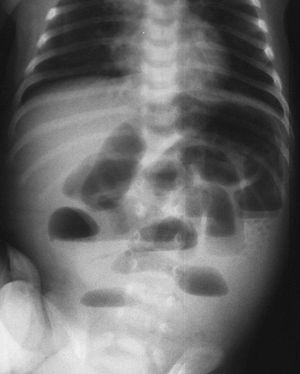

Intestinal obstruction could occur in small or larger intestine, the most common cause of all intestine obstructions is post-operative adhesions, but notice that the most common cause of large intestine obstruction is colorectal cancer in elderly people. Other causes of intestinal obstruction are henrias as femoral hernia carries the highest risk for obstruction, duodenal atresia, gallstones or paralytic ileus. Dehydration is common due to water remaining unabsorbed in the bowel or continuous vomiting. Symptoms are lack of flatus, constipation, high pitched bowel sound, nausea/vomiting, abdominal distention and tenderness. Diagnosis is by lab tests which will show elevated BUN, Hematocrit, Creatinine, LDH, CK, and in some cases WBC. This X-Ray shows dilated intestinal loops and ladder like appearence due to air-fluid levels.